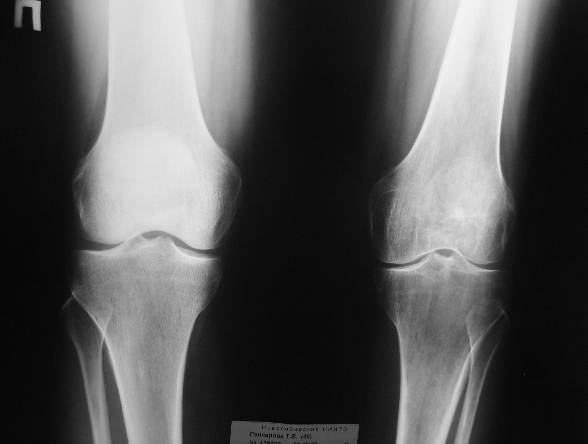

[Ortho] артроз коленного сустава

женщина 46 лет

май 2005 г заболел левый коленный сустав

Август 2005 артроскопия лечебно-диагностическая. Диагноз деформирующий

остеартроз хондромаляция1-2 степени

Февраль 2006 г артроскопическая резекция внутреннего мениска. Диагноз

застарелый разрыв внутреннего мениска на фоне гонартроза 2 степени.

Июнь 2007 артроскопия ревизия левого коленного сустава, резекция

поврежденной части внутреннего мениска, иссечение крыловидной  складки,

дебридмент коленного сустава. Диагноз застарелое повреждение

регенератавнутреннего мениска, патологическая инфрапателярная складка ,

комбинированная контрактура  левого коленного сустава, на фоне артроза 2

степени.

Октябрь 2007 МР графические признаки остеартроза коленного сустава и

бедренно-надколенного сочленения 2 степени, дистрофические изменения

сораненногозаднего рога медиального мениска и передней крестообразной

связки, кисты нижней трети диафиза бедренной кости, послеоперационных

изменений медиального  мениска.

Октябрь 2007 эндопротезирование предложили.

При осмотре  больная ходит хромая,  небольшой отек коленного сустава,

пассивные движеня в полном обьеме, активные разгибания до 160 градусов

безболезненны  далее разгибание резко болезненно . При пальпации

надколенника болезненность с внутреннего края при сдвигании его кнаружи.